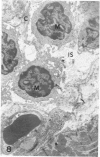

In male BALB/c mice aged 5-6 weeks inoculated three times at intervals of 15 days with 1 X 10(7) epimastigote forms of the PF strain of Trypanosoma cruzi and challenged 30 days after the last inoculation with 2 X 10(4) trypomastigote forms of the Colombia strain of T cruzi (the mice were sacrificed 80-100 days after the challenge) a cardiomyopathy very similar to that observed in the chronic phase of Chagas' disease in man develops. The cardiac syndrome is characterized grossly by cardiomegaly with hypertrophy, dilatation of ventricular chambers, and thinning of the apex of the left ventricle (apical aneurysm) and microscopically by focal areas of myocytolytic necrosis and myocardial degeneration with an inflammatory response composed of mononuclear cells (predominantly macrophages and a few lymphocytes) with concurrent interstitial fibrosis and occasional myofibers containing pseudocysts. In addition, aggregated platelets and occlusive thrombi were found in small epicardial and intramyocardial vessels of infected mice as compared with controls. The potential role of intravascular platelet aggregation in the causation of focal myocardial necrosis and degeneration and apical aneurysm in experimental T cruzi cardiomyopathy in BALB/c mice is discussed.